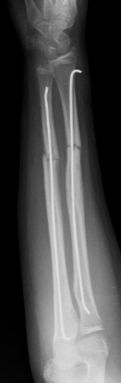

Las fracturas de ambos huesos del antebrazo al mismo nivel, con líneas de fractura oblicua-transversa o desplazamiento convergente son inestables y precisarán de tratamiento quirúrgico. En estos casos está indicado, dependiendo de la edad del paciente, el tratamiento mediante reducción y osteosíntesis. El enclavado intramedular elástico es el tratamiento de elección (Figura 15).

Figura 15: a-Imagen clínica de fractura de antebrazo derecho con gran deformidad. b- Radiografía donde se aprecia fractura de radio-cúbito de trazo transverso en el mismo nivel. c, d-Enclavado intramedular elástico. e,f- Imagen final con buena consolidación ósea.